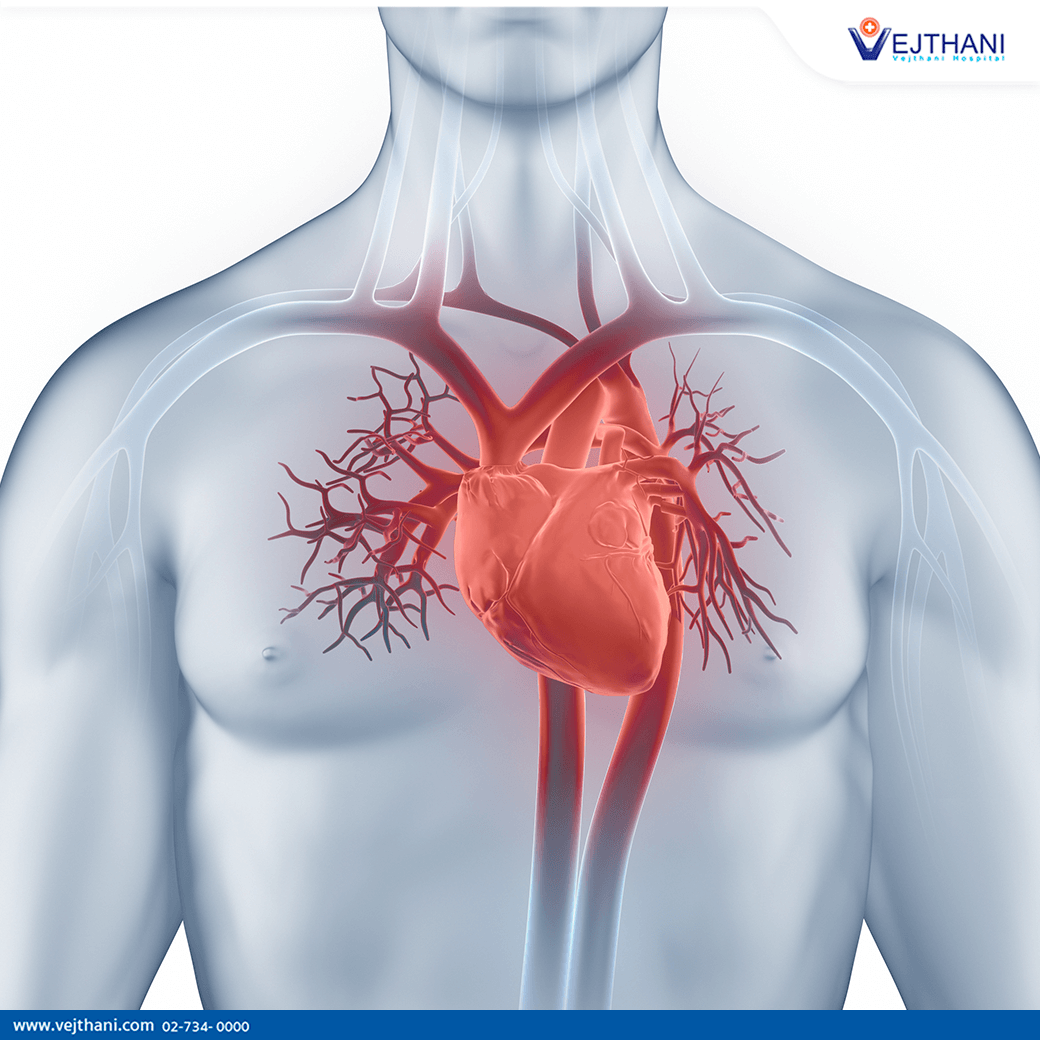

อวัยวะภายในของมนุษย์ของหัวใจที่มีระบบไหลเวียนโลหิตกายวิภาค Xray 3d … หลอดเลือดแดงและระบบไหลเวียนโลหิตของมนุษย์และกายวิภาคของหลอดเลือดดํา ภาพ …

ระบบไหลเวียนโลหิตกายวิภาคภายในในหน้าอกและหน้าท้องชาย ภาพสต็อก – ดาวน์ … ระบบไหลเวียนโลหิตโรคหัวใจและหลอดเลือดระบบอวัยวะหัวใจหลอดเลือดหัวใจ …